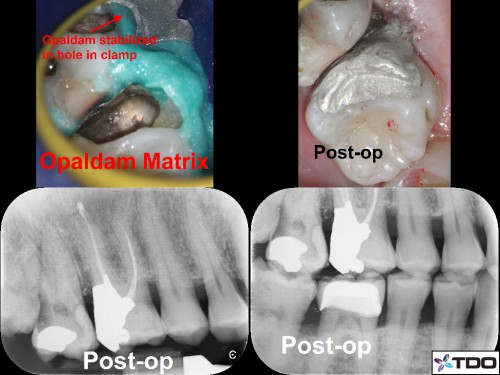

Restoring with Amalgam. 72yom. The patient had avoided the dentist due to dental anxiety. Tooth #3(16) SIP and #2(17) responded normally to all clinical tests. I recommended attempting to save both molars but he hesitantly agreed to start with tooth #3. Image Guided Treatment using CBCT aided in confirming the presence and location of MB2. The Opaldam matrix, first described by Dr. Michael Trudeau, is useful when using amalgam to restore teeth with deep interproximal caries especially when one or more corners are lost. In the end, the patient elected to extract the second and third molars and the amalgam restoration was incorporated into a Deep Margin Elevation for crown placement.